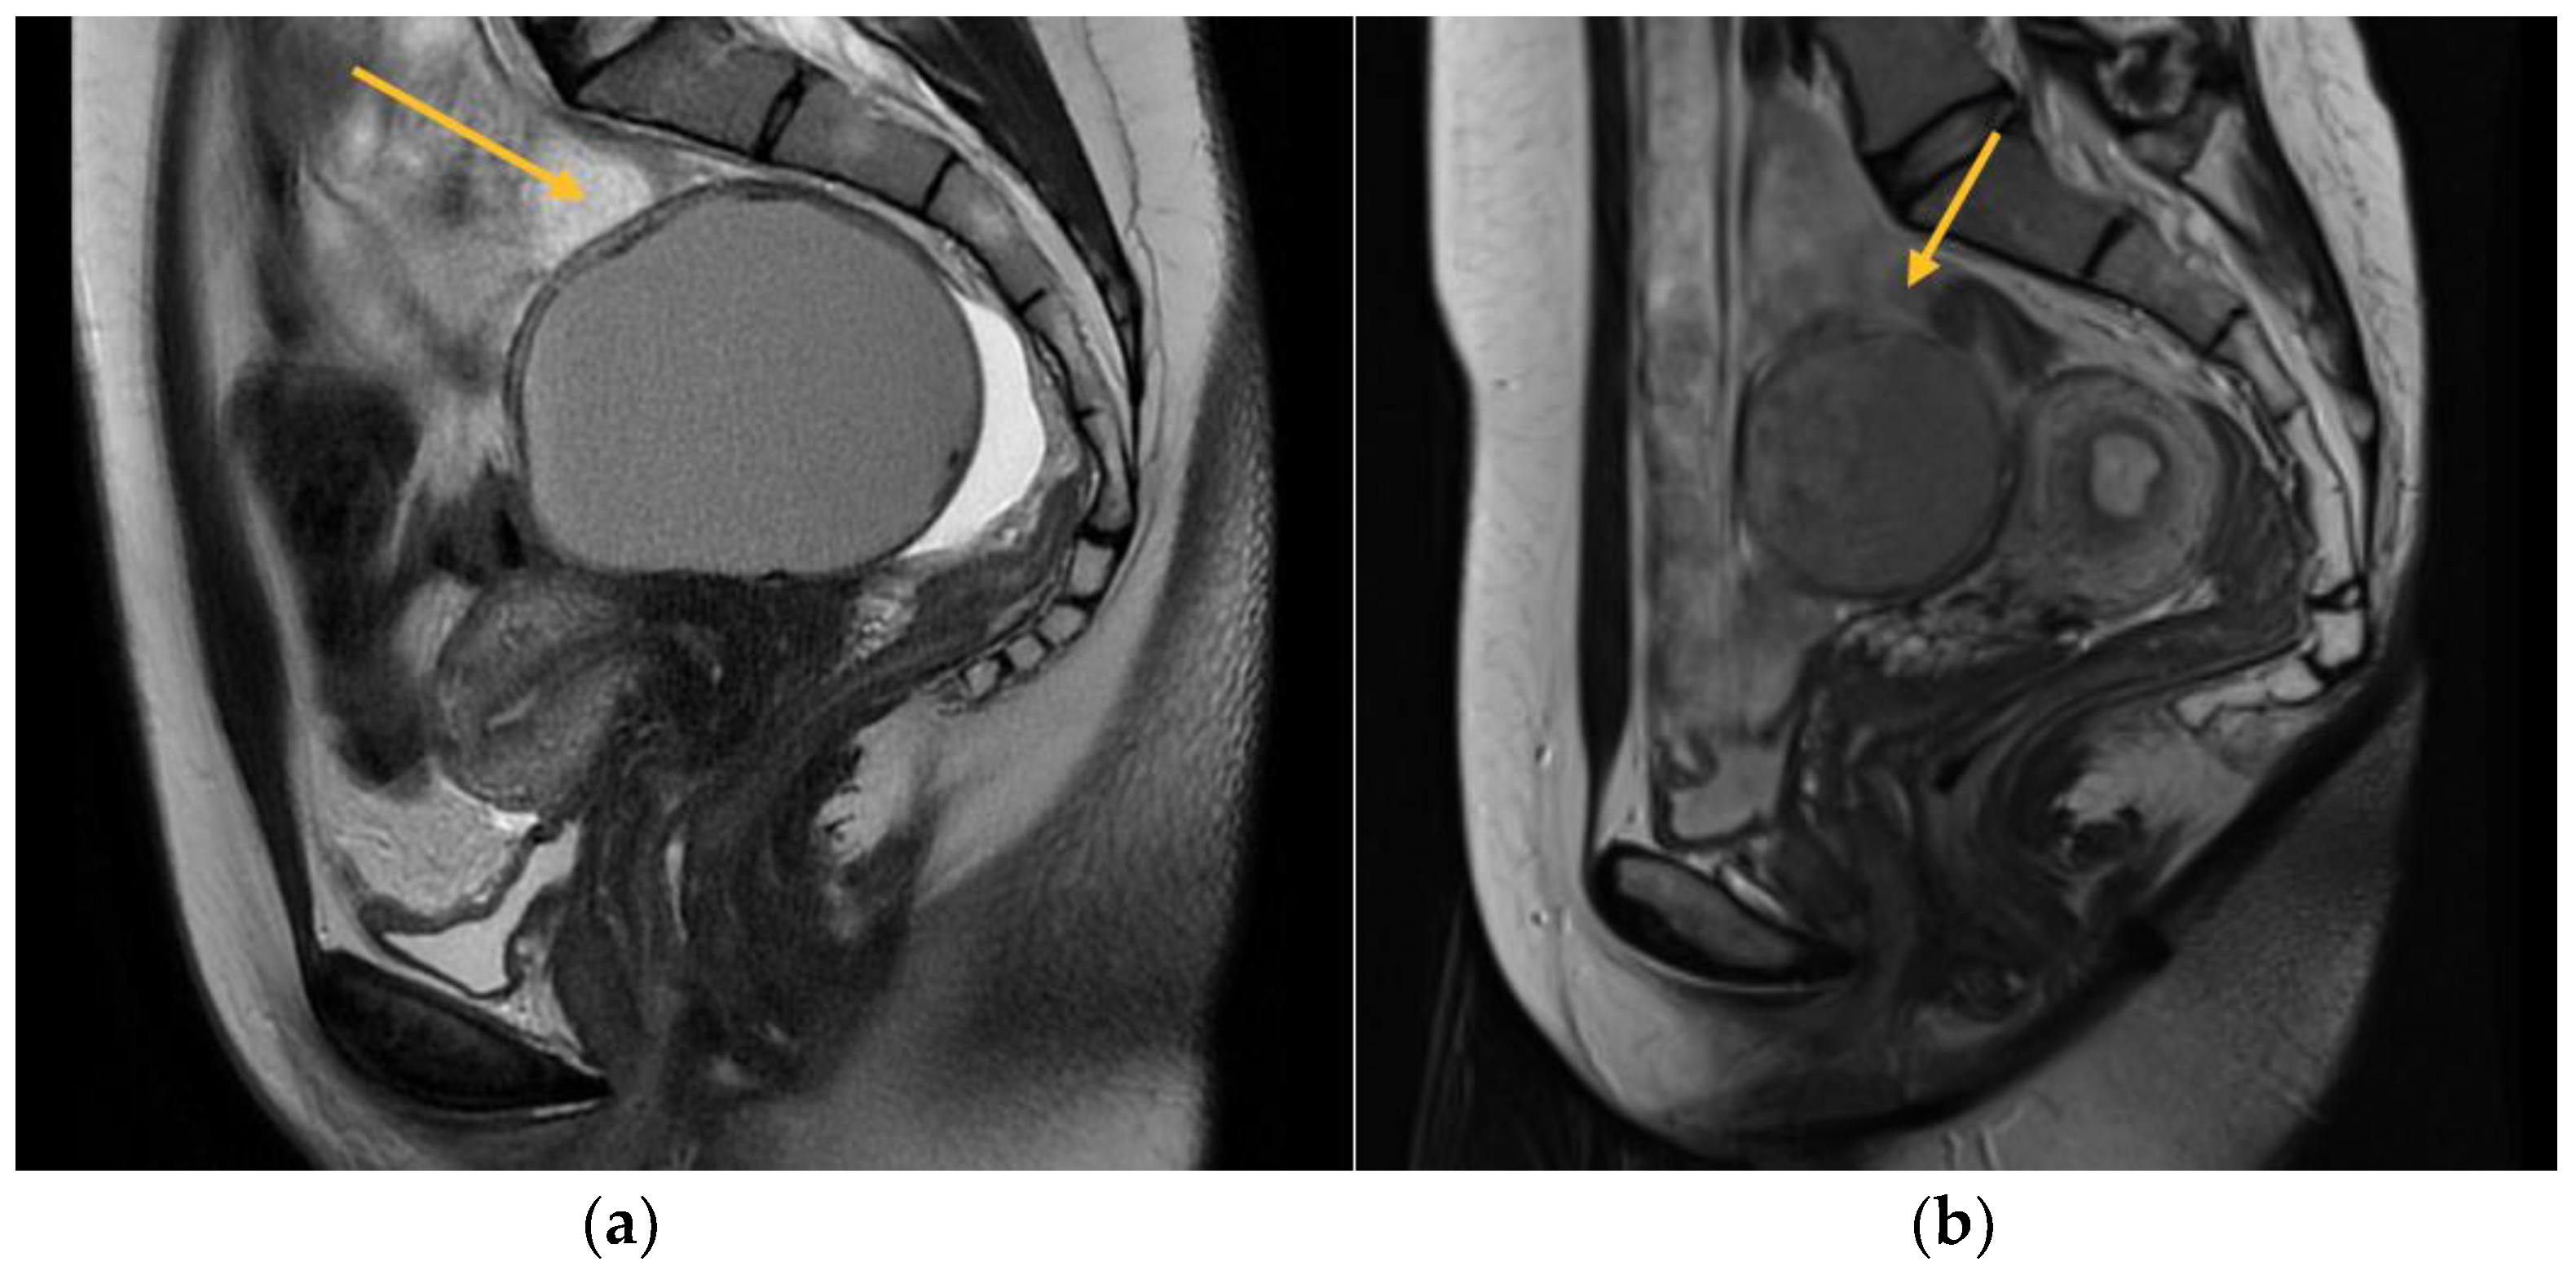

2.3. Magnetic Resonance Imaging

MRI is commonly utilized as an additional diagnostic method subsequent to TVS in order to obtain a precise anatomical representation of the pelvic organs. It has been found to possess the highest overall accuracy in detecting the extent of deep infiltrating endometriosis [5]. In the present study, a total of 256 patients were evaluated, out of which 177 underwent a 3.0 Tesla MRI scan. The exclusion criteria for MRI included personal factors such as claustrophobia, anxiety, and obesity. Additionally, patients who had already received a definitive diagnosis of endometriosis through TVS, those for whom an MRI examination was deemed unnecessary, and individuals with financial constraints limiting their ability to afford the high cost of the investigation were also excluded. To conduct a comprehensive assessment of the pelvic compartments and structures, a volume of 40 mcm3 of lubricant gel was introduced into both the vagina and rectum. This was done with the aim of augmenting the visualization and understanding of the pelvic anatomy. This approach enhances the perceptibility of the walls and potential endometriosis nodules, facilitating the quantification of the extent of infiltration (Figure 1).

Figure 1. MRI aspect on T2 sagittal (a) Left endometrioma with left ovary adherent to the posterior uterine wall (b) Right endometrioma.